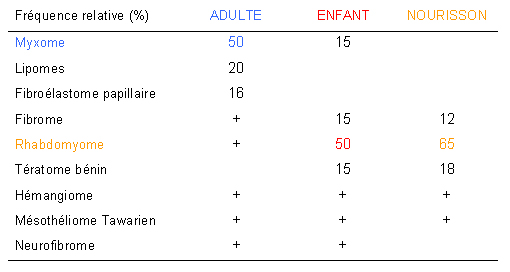

PRÉVALENCE DES LOCALISATION SECONDAIRES CARDIAQUES

Les tumeurs cardiaques secondaires sont 20 à 40 fois plus fréquentes que les tumeurs primitives. Des métastases cardiaques sont retrouvées à l’autopsie des patients traités pour cancer dans 2 à 18% des cas, selon les séries. (Monsuez et al, EMC Cardiologie, 11-048-C-10, 2008). Les mélanomes entrainent des métastases cardiaques le plus fréquemment (71%). Les localisations secondaires cardiaques sont observées – par ordre décroissant de 30 à 1O% environ – en cas de cancer bronchique, du sein, de l’oesophage, de l’utérus, ORL, du rein et des ovaires. Les lymphomes non hodgkiniens s’accompagnent de métastases cardiaques dans 13% des cas et les leucémies dans 6% des cas.